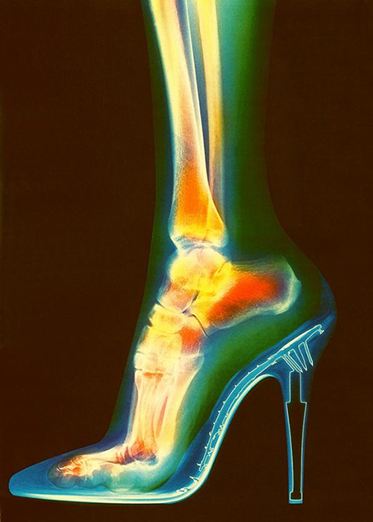

Οι γυναίκες λατρεύουν τα ψηλοτάκουνα παπούτσια τους τόσο πολύ, σε σημείο που να θυσιάζουν τα πόδια τους για πάντα. Οι γυναίκες που φορούν τακούνια στους 5 και πάνω πόντους, κάνουν τα πόδια τους να φαίνονται μακρύτερα και τονίζουν το σχήμα της γάμπας τους. Δυστυχώς, η συχνή χρήση αυτού του είδους υποδημάτων μπορεί να προκαλέσει πολλαπλά ορθοπεδικά προβλήματα με την πάροδο του χρόνου.

Τα μετατάρσια οστά επιβαρύνονται πολύ, καθώς παίρνουν τον ρόλο του υποστηρικτή, ενώ το υπόλοιπο πέλμα, που στηρίζεται στην πολύ μικρή βάση του τακουνιού, φθείρεται πρόωρα και πονάει συνεχώς. Επιπλέον, τα δάχτυλα «στραγγαλίζονται» και σπρώχνονται μπροστά, με αποτέλεσμα να παρουσιάζονται κάλοι και επώδυνες παραμορφώσεις. Συχνά, εξαιτίας της υπερβολικής πίεσης, τα νύχια μεγαλώνουν προς τα μέσα.

Γόνατα: Είναι η μεγαλύτερη και η πιο ταλαιπωρημένη άρθρωση στο σώμα, αφού σε κάθε μας βήμα δέχονται κραδασμούς με διπλάσια έως τριπλάσια δύναμη από το βάρος μας. Τα ψηλά τακούνια μπορεί να προκαλέσουν πρόωρη αρθρίτιδα στο γόνατο. Το περπάτημα σε ψηλά παπούτσια επιβαρύνει περισσότερο την κατάσταση, καθώς λόγω της λανθασμένης θέσης της επιγονατίδας οι χόνδροι φθείρονται γρηγορότερα. Επειδή η χρήση τους προκαλεί αφύσικη στάση φέροντας την σπονδυλική στήλη την λεκάνη και τα ισχία προς τα εμπρός, προκαλείται ανώμαλη φόρτιση στο εσωτερικό του γονάτου, συμβάλλοντας στην πρόωρη φθορά του χόνδρου που έχει σαν αποτέλεσμα την ανάπτυξη της οστεοαρθρίτιδας. Μπορεί επίσης να πάθουμε κάτι ήπιο και παροδικό, όπως ένα διάστρεμμα ή ένα τράβηγμα, μέχρι κάτι πιο σοβαρό, όπως τενοντίτιδα, αρθροθυλακίτιδα.

Αστράγαλοι: Φορώντας τακούνια, οι αστράγαλοι ωθούνται προς τα εμπρός. Η ώθηση αυτή περιορίζει την κυκλοφορία του αίματος στα κάτω άκρα και μπορεί να προκαλέσει μέχρι και ευρυαγγείες. Όλα τα ψηλά τακούνια είναι η κύρια αιτία ενός διαστρέμματος στον αστράγαλο. Το πιο κοινό πρόβλημα είναι το πλευρικό διάστρεμμα, που μπορεί να σχίσει τους συνδέσμους.

Η χρήση παπουτσιών στιλέτο με τακούνι άνω των 5 εκατοστών φορτίζει το πρόσθιο μέρος του ποδιού ίσο με τρεις φορές το βάρος του σώματος και η χρήση αυτών των παπουτσιών για μεγάλο χρονικό διάστημα άνω αυτού του ύψους μπορεί να προκαλέσει την ανάπτυξη πολλών χρόνιων προβλημάτων.